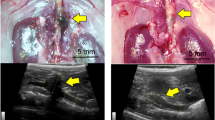

Observing elevated ILF3 levels in AAA, particularly in macrophages, we investigated macrophage ILF3 overexpression’s impact on AAA using ILF3 conditional overexpression mice (ILF3Flox/FloxLysMCre+; hereafter referred to as ILF3M-Tg) and its littermates (ILF3Flox/FloxLysMCre-; hereafter referred to as ILF3M-WT) in an ApoE−/− background (Supplementary Figs. 3A–3D). Following a 4-week saline infusion, no aneurysms were observed in either group (Fig. 2A). However, under Ang II induction, both groups experienced a significant rise in systolic blood pressure with Ang II, with no differences between the ILF3M-TgApoE−/− and ILF3M-WTApoE−/− mice (Supplementary Table 2). Notably, ILF3M-TgApoE−/− mice displayed more pronounced aortic dilation compared with ILF3M-WTApoE−/− mice (Fig. 2A). The incidence of AAA formation (Fig. 2B) and the rupture rate of AAA (Fig. 2C) in ILF3M-Tg ApoE−/− mice was markedly higher than that of ILF3M-WT ApoE−/− group through the 4-week Ang II exposure. Among those subjected to Ang II infusion, 68.75% (22/32) of ILF3M-Tg ApoE−/− mice died, apparently higher than the mortality rate of ILF3M-WT ApoE−/− (37.50%, 12/32; Fig. 2D). Vascular ultrasound imaging and maximal external aortic diameter detection further corroborated these findings, revealing more pronounced dilation in the ILF3M-Tg ApoE−/− mice post-Ang II infusion (Fig. 2E; Supplementary Fig. 3E). Histological analysis indicated no elastin disruption under baseline conditions; however, ILF3 overexpression in macrophages significantly exacerbated elastin degradation in Ang II-induced AAA models (Figs. 2F, G).

The 8-week-old male ILF3M-Tg ApoE−/− and ILF3M-WTApoE−/− mice were infused with Ang ll or saline (sham group). A Schematic representation of study design and representative images showing the morphology of the whole aorta from all groups showing the macroscopic characteristics of aneurysms. B–D The AAA incidence (B) rupture rate (C) and Kaplan-Meir survival curve (D) across different groups (sham group, n = 6; Ang II group, n = 32). Statistical analyses employed a chi-square test with a two-tailed analysis for (B, C) and the Log-rank test for (D). E Representative ultrasound images of aorta across different groups (sham group, n = 6; Ang II group, n = 12). F and G Representative hematoxylin and eosin (HE) and Verhoeff-Van Gieson (VVG) staining (F) and elastin degradation grading (G). (sham group, n = 5; Ang II group, n = 12; Scale bar=100 μm). 8-week-old male ILF3M-Tg and ILF3M-WT mice were infused with CaCl2 or saline (sham group). H and I Schematic representation of study design and representative photographs (H) of saline-treated and CaCl2-induced aneurysm and maximal abdominal aortic diameter (I; sham group, n = 6; Cacl2 group, n = 12). Data are represented as mean ± SD. For comparisons between two groups, an unpaired Student’s t-test with two-tailed analysis (2G and 2I). Boxplots were created using the first and third quartiles to define the bounds of the box, with the median shown in a circle. The minima are defined as the first quartile minus 1.5 times the inter-quartile range (IQR), and the maxima are defined as the third quartile plus 1.5 times the IQR. Violin plots display the density distribution of the data points through smoothed histograms.

To further validate the role of macrophage ILF3 in AAA, we evaluated the effects of macrophage ILF3 overexpression in CaCl2-induced AAA model mice. Consistent with the results observed in Ang-II-induced AAA model mice, ILF3M-Tg mice were more susceptible to abdominal aortic dilation with increased maximal abdominal aortic diameter in CaCl2-induced AAA model (Figs. 2H, I). Moreover, HE and VVG staining showed that elastic lamellae of ILF3M-Tg mice were disrupted and degraded to a greater extent than that of ILF3M-WT mice (Supplementary Figs. 3F, G). Collectively, these results underscore the pivotal role of macrophage-derived ILF3 in promoting AAA formation and progression in both CaCl2- and Ang II-induced models.